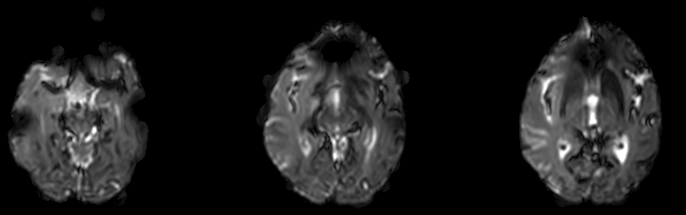

[Python] Brain MRI Thresholding 본문

★ My application

extract brain region in brain MRI image to improve computational efficiency

3) generate binary removing noise

# generate mask

mask = np.zeros_like(tmp0)

for j in range(tmp0.shape[0]):

# mask[j] = tmp[j] > thr

mask[j] = closing(dilation(erosion((tmp0[j] > thr), se), se), se)'Programming > Medical Image Processing' 카테고리의 다른 글